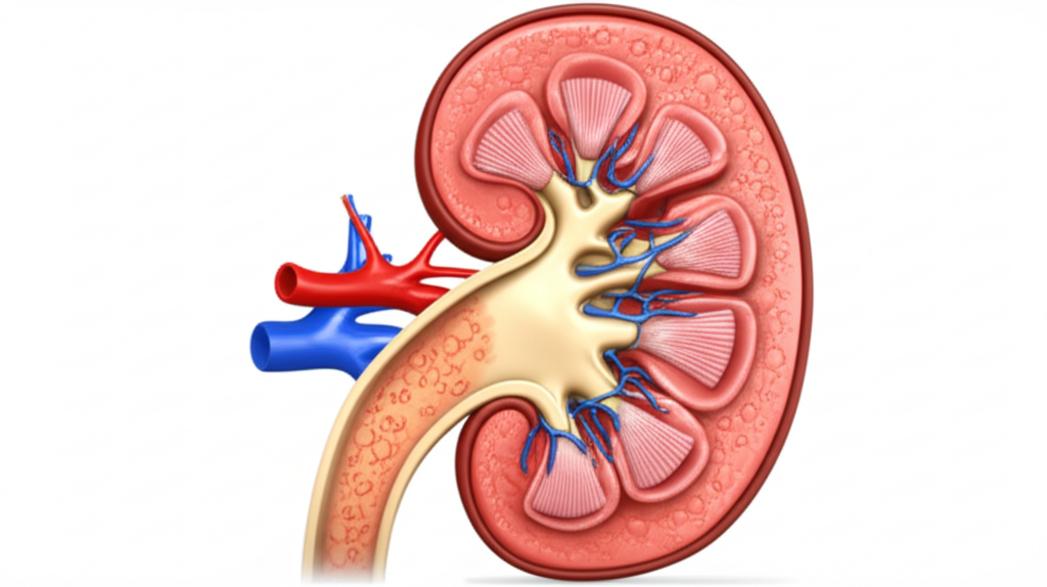

กลไกการทำงานของไตและสาเหตุของการเสื่อม

ไตมีหน่วยกรองเล็กๆ นับล้านหน่วยที่เรียกว่า “เนฟรอน” ทำหน้าที่เป็นตัวกรองหลัก ภาวะไตเสื่อมเกิดขึ้นเมื่อเนฟรอนเหล่านี้ได้รับความเสียหายหรือถูกทำลายจนไม่สามารถทำงานได้เต็มที่ สาเหตุหลักๆ ที่นำไปสู่ภาวะไตเสื่อมมีความซับซ้อนและสัมพันธ์กันหลายปัจจัย:

การทำความเข้าใจสาเหตุและกลไกเหล่านี้เป็นก้าวแรกที่สำคัญในการวางแผนการดูแล เพื่อชะลอการดำเนินของโรคและป้องกันไม่ให้ไตเสื่อมสู่ระยะสุดท้าย